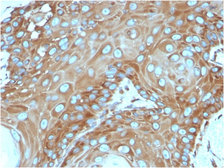

Product

Images

Description

Applications

Reactivity